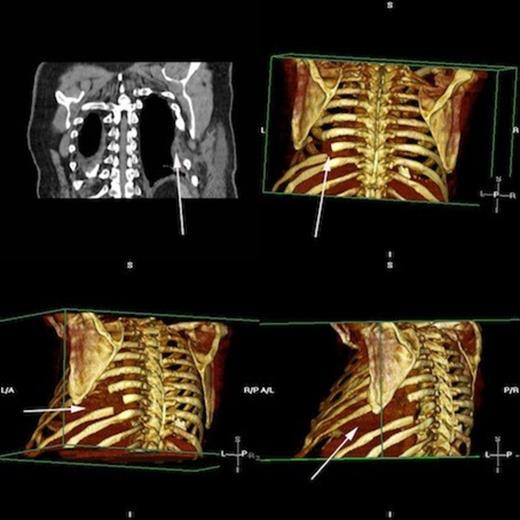

A CXR scan was performed which illustrated atelectasis at his left lung base. A subsequent CT demonstrated intercostal lung herniation alongside fractured sixth, seventh and eighth ribs, arising as a result of chest wall deformity (figure 1). Images were subsequently reconstructed by a clinical radiologist to fully demonstrate the skeletal pathology. (figure 2)

Rendered images of fractured ribs 6, 7 and 8 Arrowheads demonstrating fractures of the left 6th, 7th and 8th ribs. * = site of skeletal defect and subsequent site of pulmonary herniation

Postoperative progress was satisfactory and without complication, with the patient receiving daily input from the surgical, anaesthetic and physiotherapy teams. A repeat CT scan following the procedure confirmed restoration of the hernial defect and correction of the pulmonary hernia (figure 9).

Postoperative rendered images confirming restoration of herniated lung Top left, CT demonstrating PermacolTM patch in situ. Rendered images display areas of resected ribs and the revised bony form. Lung is restored and shows no evidence of herniation.